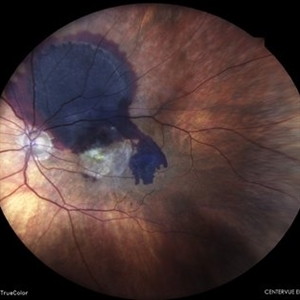

TRACTIONAL RETINAL DETACHMENT

COLOUR FUNDUS WIDE-FIELD PHOTO OF A 50 YEAR OLD DIABETIC MALE WITH TRACTIONAL RETINAL DETACHMENT, SUB-HYALOID HEMORRHAGR AND ASTEROID HYALOSIS IN A CASE OF PROLIFERATIVE DIABETIC RETINOPATHY

Photographer: Dr. Akansha Sharma-Retina Foundation, Ahmedabad

Condition/keywords: asteroid hyalosis, florid type PDR, proliferative diabetic retinopathy (PDR), SHH, subhyaloid hemorrhage, TRD